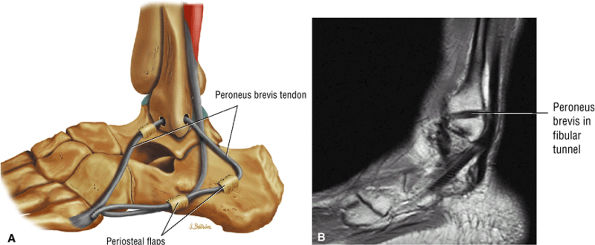

|

![]() |